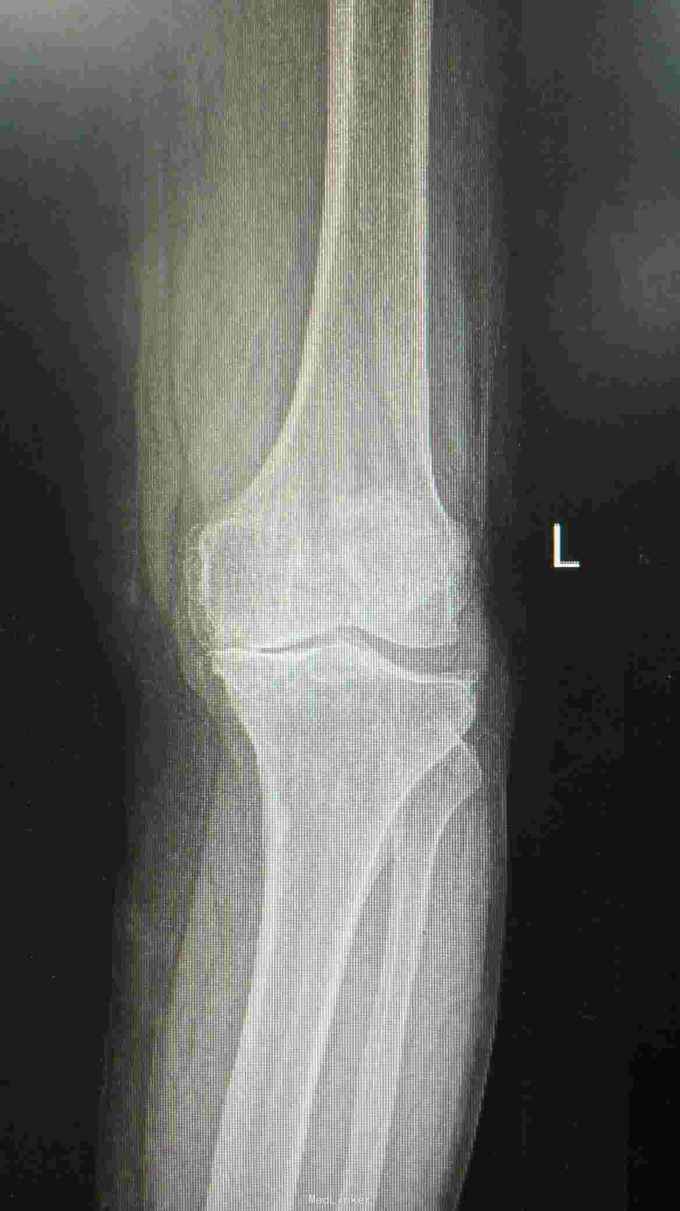

76岁女性,左膝关节疼痛5年,加重1月。平时以活动痛为主,最近一月疼痛明显,影响行走。既往体检。

左膝轻度内翻畸形,皮温稍高,膝关节前内侧压痛阳性,内外侧方应力试验阴性,前后抽屉试验阴性。屈伸活动度0---110度。 入院辅助检查:血常规、ESR、CRP、PCT均在正常范围。心肺功能可。

诊断:左膝关节骨性关节炎 治疗:左膝关节单髁置换术